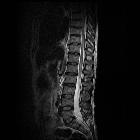

Spinal astrocytomas usually span multiple segments in craniocaudal extent, with an average length of involvement of 4-7 vertebral body segments .

Regarding their specific spinal location:

- involvement of thoracic cord (67%), followed by cervical cord (49%), are most common. Tumor may, of course, involve both regions

- involvement of entire spinal cord (holocord presentation) - more common in children than in adults

Astrocytomas are typically intramedullary masses that diffusely expand the spinal cord. They usually span spinal multiple segments, as discussed above. Their slow outward growth tends to cause osseous remodeling of the spinal canal, which may be the only clue to their presence on x-ray or CT.

As astrocytomas arise from cord parenchyma (c.f. ependymomas that arise in the central canal), they typically have an eccentric location within the spinal cord.

They may be exophytic and even appear largely extramedullary. They usually have poorly defined margins. Peritumoral edema is present in ~40%. Intratumoral cysts are present in ~20% and peritumoral cysts are present in ~15%. Unlike ependymomas, hemorrhage is uncommon.